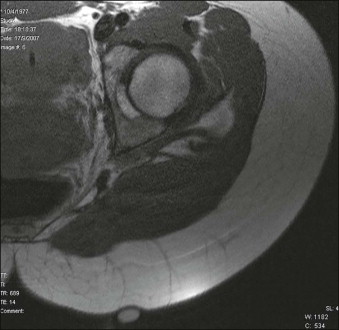

In 2009, a study employing magnetic resonance imaging (MRI) showed the presence of thick subcutaneous septa in about 97% of the depressed lesions typical of cellulite, as evidence of its pathogenesis in this condition. These septa displayed a tree-like morphology. Furthermore, the T2 images also showed the presence of vessels together with the septa ( Fig. 16.1 ).